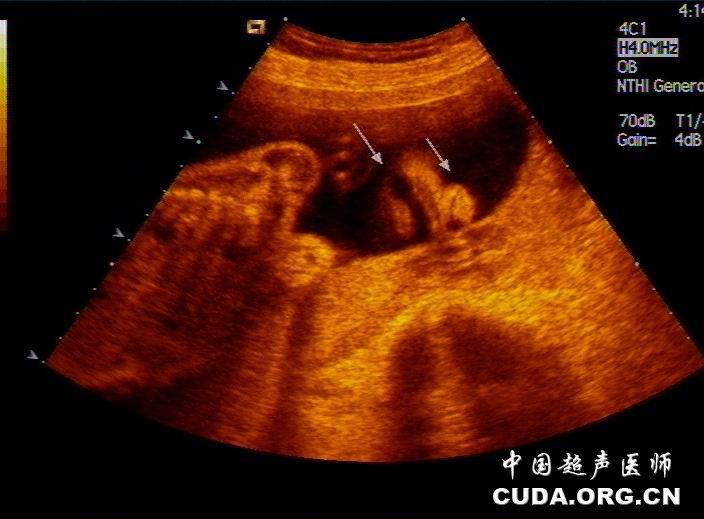

胎儿唇腭裂伴面横裂畸形产前超声表现一例

图片尺寸2008x650